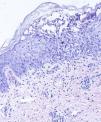

Presentamos el caso de una niña nacida a término con fenotipo Down y un exantema vesiculopustuloso de predominio facial, con lesiones distribuidas de forma irregular sobre la cara, el cuero cabelludo y el tronco (fig. 1). No se realizó ningún control del embarazo hasta la segunda mitad del mismo, observándose entonces en la ecografía anomalías cardiacas leves. El síndrome de Down se confirmó mediante cariotipo en la primera semana de vida. En la analítica realizada el primer día de vida se encontró: hemoglobina de 22,7g/dl, 46.000 plaquetas/μl y 49.000 leucocitos/μl con 28% de blastos en sangre. Los cultivos para bacterias, hongos y virus fueron negativos. En el frotis de una de las pústulas se observaron elementos granulocíticos maduros, intermedios y algún blasto. La médula ósea no presentaba signos de leucemia. En la biopsia cutánea se encontró una vesiculopústula subcórnea, repleta de leucocitos polimorfonucleares, con presencia de exocitosis epidérmica de dichos elementos (fig. 2). Tanto las alteraciones hematológicas como las lesiones cutáneas se resolvieron espontáneamente en las primeras semanas de vida.